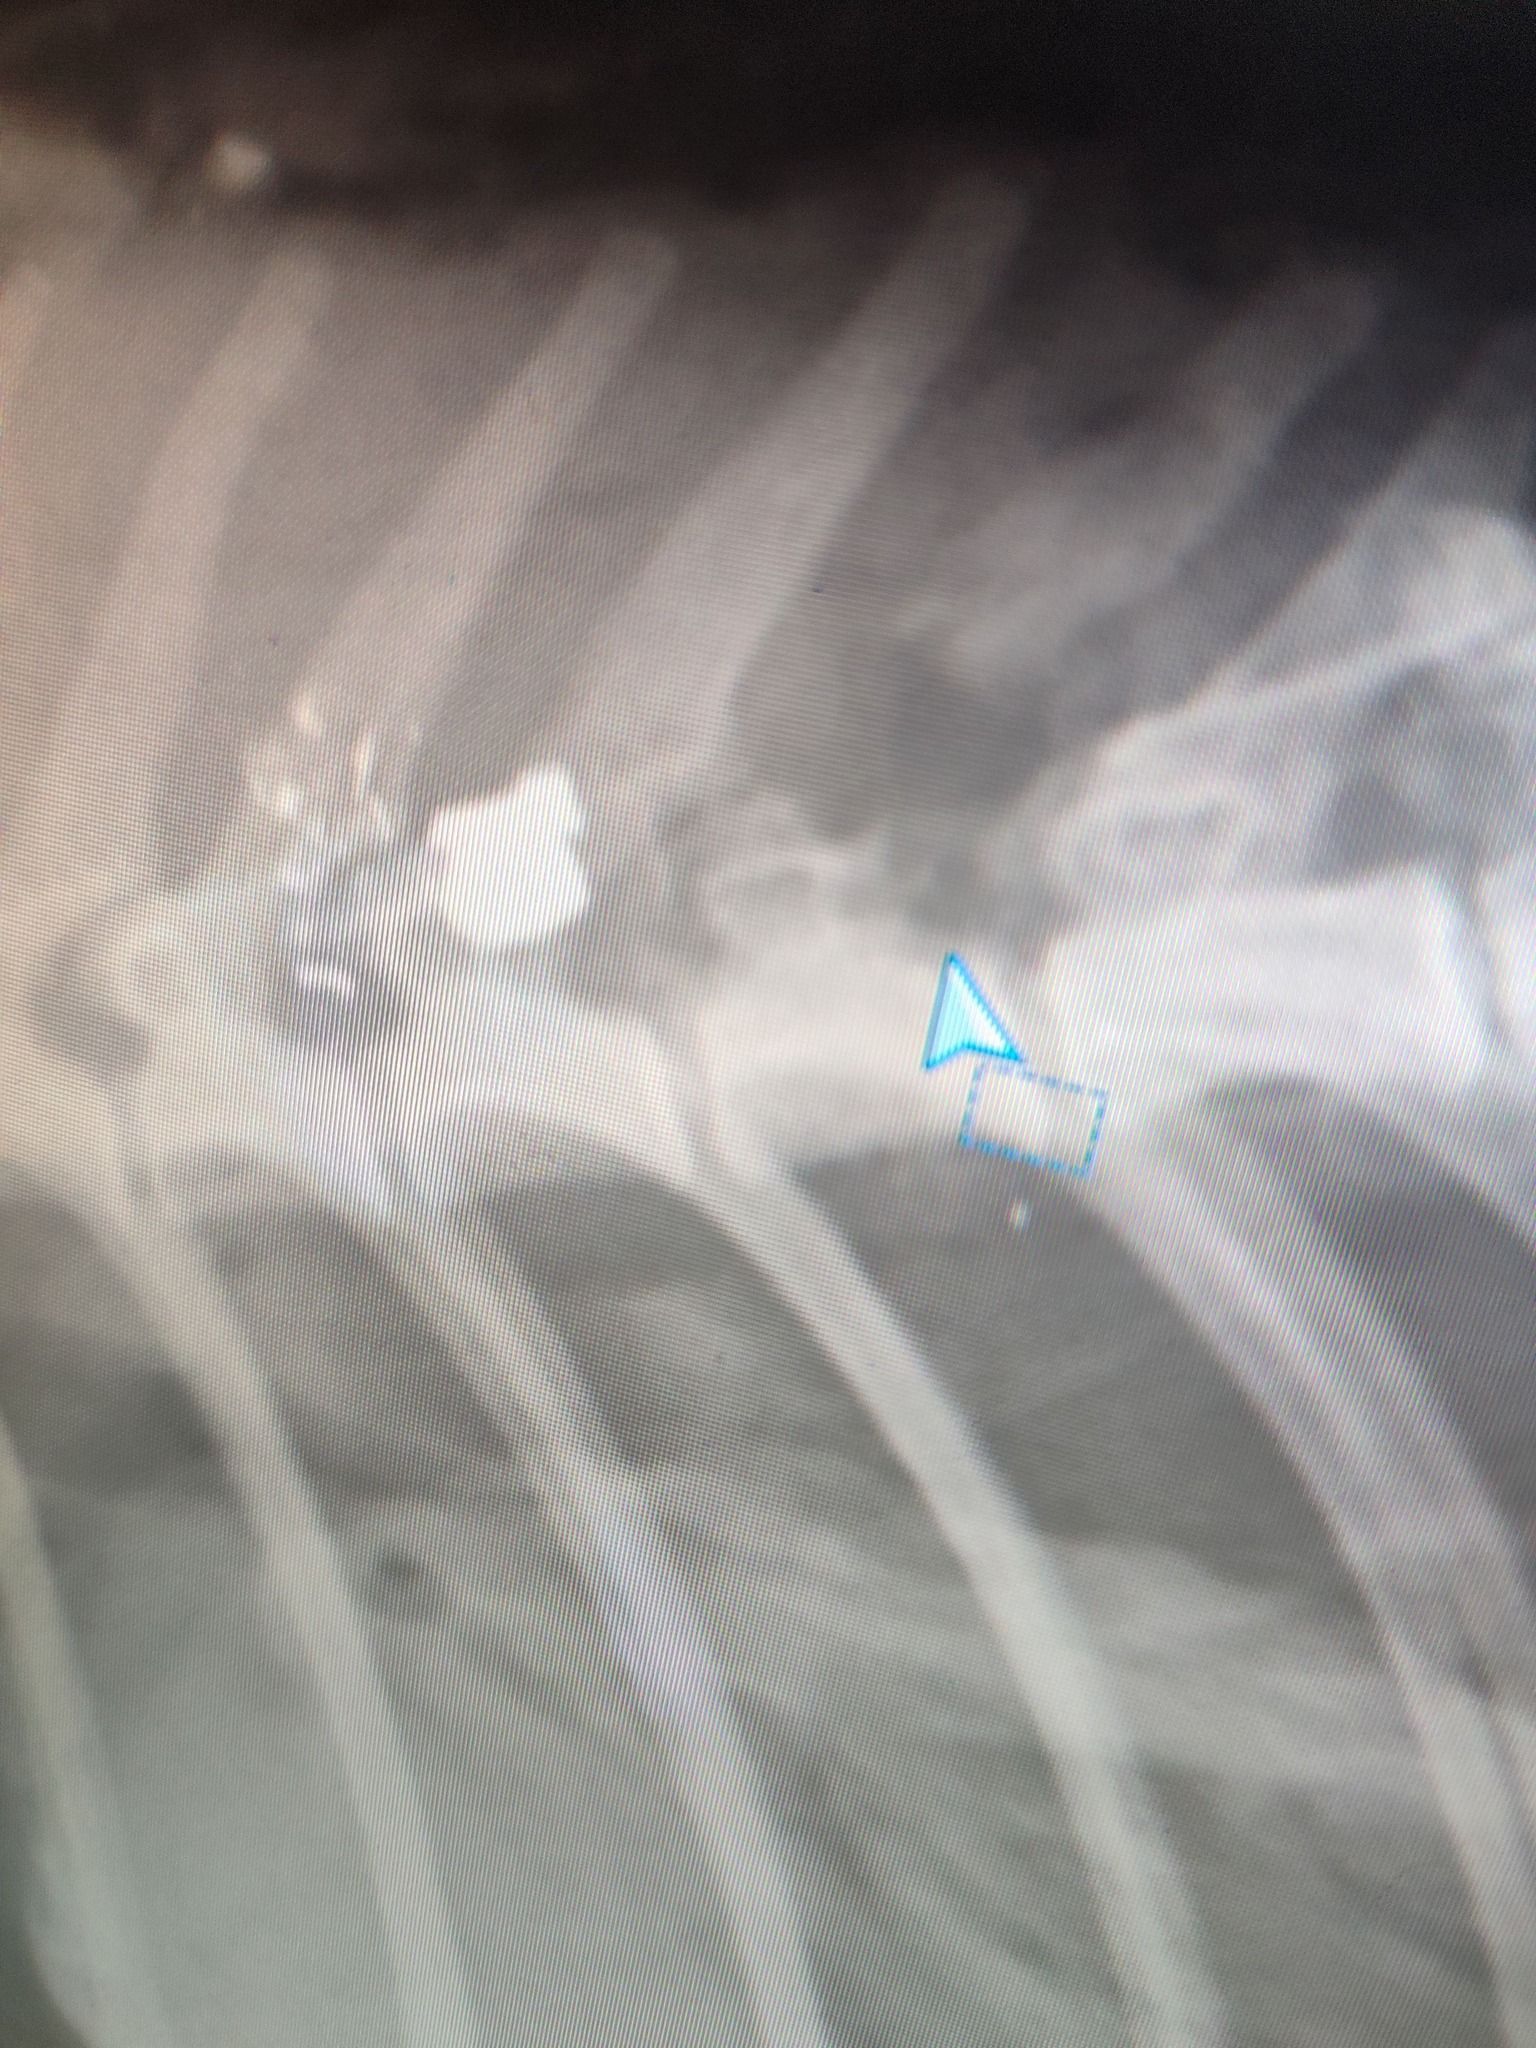

Το ζώο, όπως έδειξαν οι ακτινογραφίες, είχε πυροβοληθεί με αεροβόλο δύο φορές. Το ένα σφαιρίδιο είχε καρφωθεί στην σπονδυλική του στήλη και αν δεν είχε πάει επί τόπου ο εθελοντής διασώστης Κώστας Μαμασούλας, ώστε και να το πιάσει και να το μεταφέρει σε κτηνιατρική κλινική, η γάτα θα ήταν ήδη νεκρή και θα είχε μαρτυρικό θάνατο…

Οι πιθανότητες να περπατήσει είναι λιγες, ωστόσο αποφασίστηκε να κάνει το χειρουργείο και να του δώσουμε έστω αυτή την μικρή πιθανότητα ώστε να βγει η σφαίρα που είχε σφηνώσει στην σπονδυλική στήλη και να αποσυμπιεστεί. Τώρα το μόνο που μας μένει είναι να περιμένουμε, καθώς είναι πολύ δύσκολο ζώο και καθόλου συνεργάσιμο.».